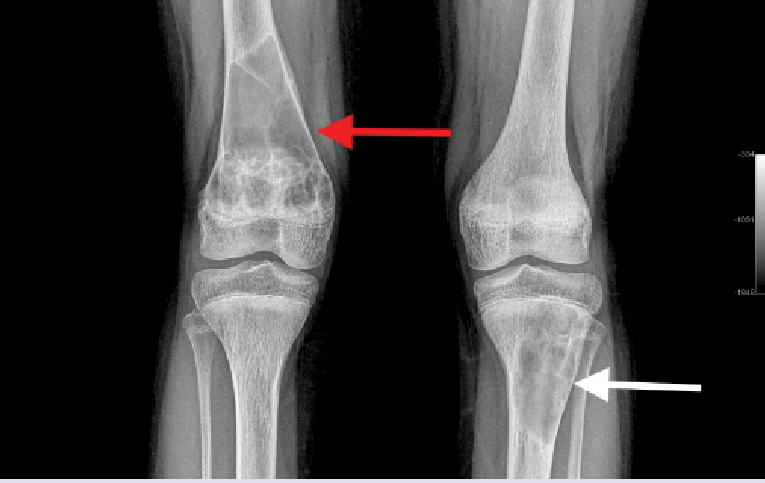

- The classic manifestation of PHPT bone disease is:

- Osteitis fibrosa cystica:

- Which is characterized clinically by bone pain and radiographically by subperiosteal bone resorption

- It has pathognomonic radiological findings:

- Brown or osteoclastic tumors of the long bones:

- Result from excess osteoclast activity:

- And consist of collections of osteoclasts intermixed with fibrous tissue and poorly mineralized woven bone

- The brown coloration is due to:

- Hemosiderin deposition